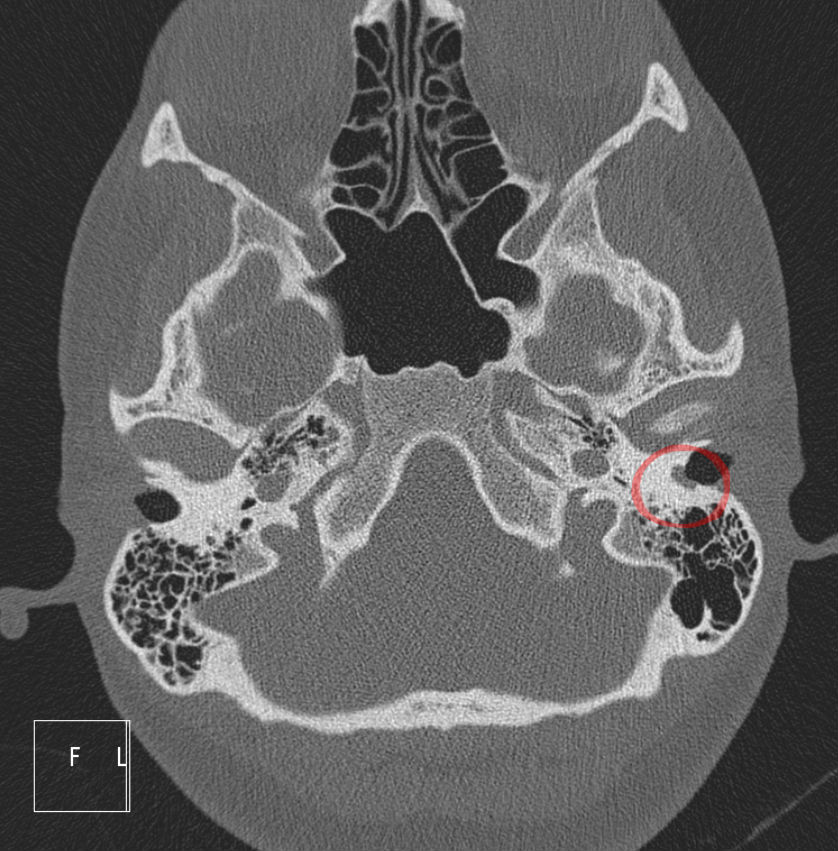

Cholesteatomas can be diagnosed by observation with an otoscope, CT scan, and hearing test audiograms. Once diagnosed, treatment entails the surgical removal of the skin growth. Follow up is necessary to ensure that the growth does not return and occasional ear cleaning by a healthcare professional may be needed. Secondary surgeries can occur if the growth is not fully removed or returns after an initial surgery.